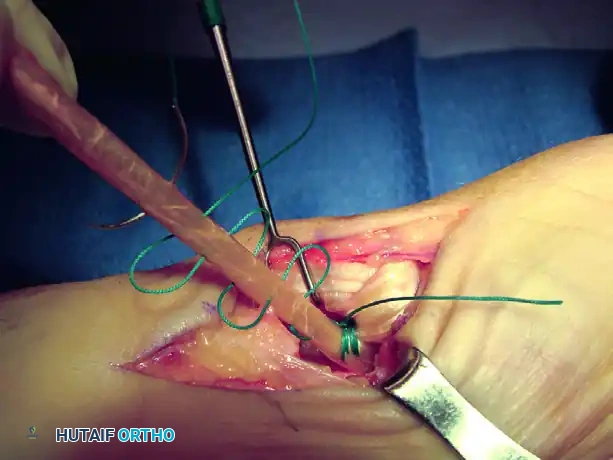

Intraoperative view demonstrating the creation of the metacarpal tunnel.

Intraoperative view of the FCR tendon strip harvested and prepared for routing.

Intraoperative view showing the tendon strip being pulled dorsally through the metacarpal tunnel.

Intraoperative confirmation of joint reduction and K-wire placement.

Intraoperative view of the final tendon weave and capsular reinforcement.

Intraoperative view of the trapezial void and preparation of the metacarpal base.

Intraoperative view demonstrating the suspension of the first metacarpal.